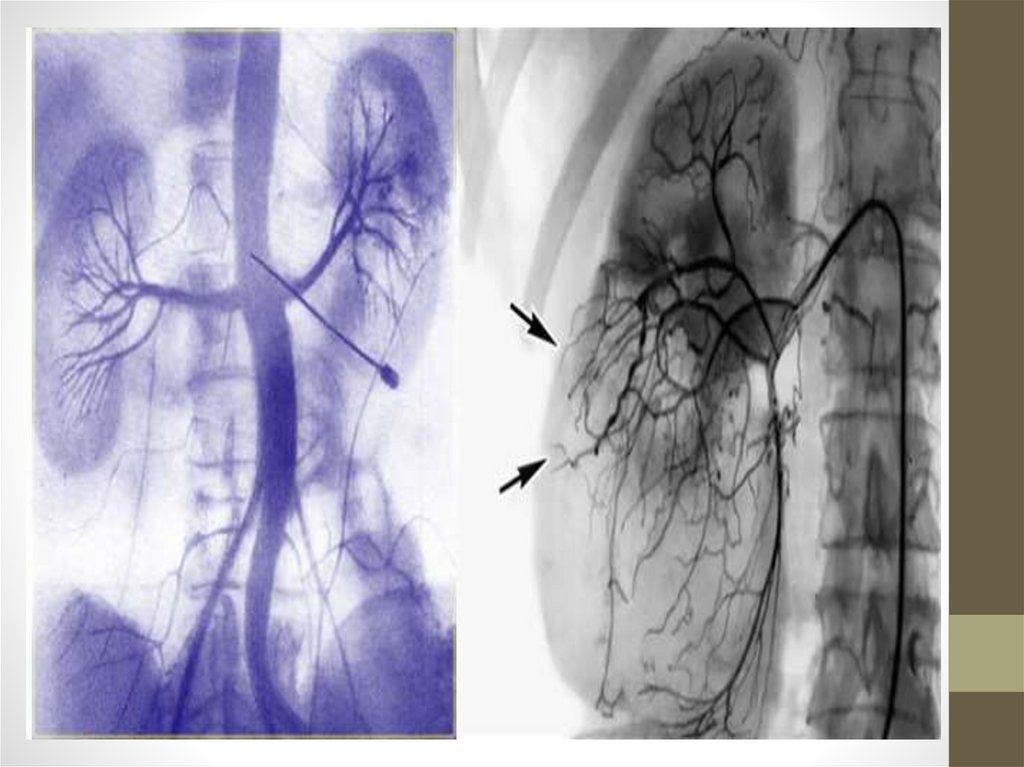

• Инструментальные: УЗИ, сканирование. КТ, МРТ,

ангиография почечных артерий.